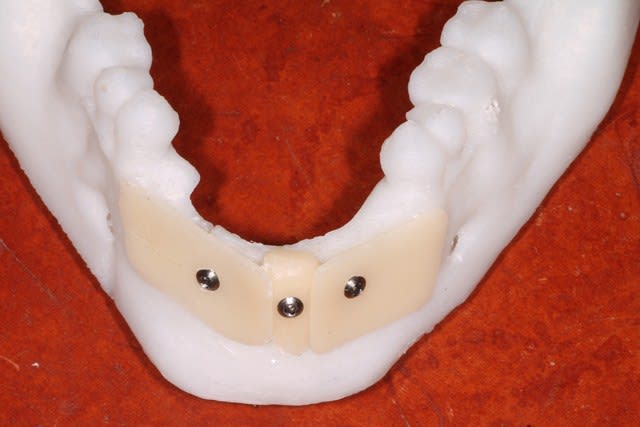

Voici 3 possibilités traité sur la maquette mandibulaire.

2 blocs biobank 20x10 :700 € + membrane et vis

Coffrage avec prélèvement ramique : biomateriaux + vis , de la membrane et de la sueur .

Coffrage avec membrane en PDLLA 126x11x0,8mm :300 € ttc + biomatériaux ( autogene + minéros, c'est pas mal ) + vis d'espacement et de fixation + membrane collagene ( http://www.biagginimedical.com/#!sonicweldrx/civk )

L'étude me fait éliminer le coffrage ramique, car je me retrouve avec une assez faible épaisseur au niveau de 32 42, ( sans parler de la difficulté du prélèvement, vu le peu d'os disponible ).

Reste les blocs, et un coffrage en adaptant la technique sonicweldrx en fixant la membrane PDLLA avec des vis d'ostéosynthèse.

j'avais cru voir dans un kit de vis, des vis d'espacement avec une minivis dans la tête, pour fixer la membrane , mais je ne sais pas si j'ai rêvé, je ne retrouve pas le site web correspondant ( voir mon schéma )

Je pour la forme, faut 2 vis par bloc, sinon ça bouge...